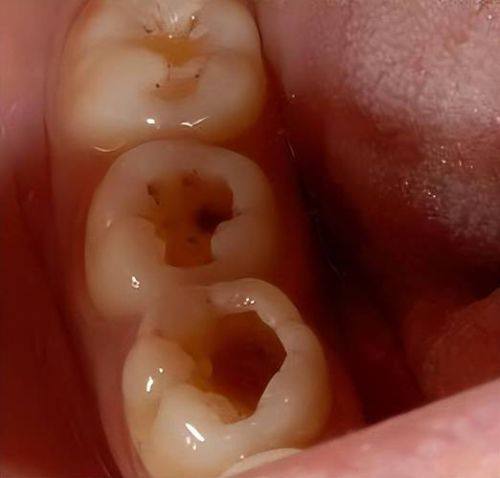

当龋坏发展到牙本质浅层时,就进入了中龋阶段。这个时候患者虽然不会有自发的疼痛,但对冷、热、酸、甜等刺激会有反应。比如吃了一口冰淇淋或者喝了一口热水,牙齿可能会出现一过性的疼痛,不过这种疼痛持续时间特别短,仅仅只有几秒,而且当刺激因素去除后,疼痛马上就会停止。在临床检查中,医生可以探及明显的龋洞,用探针触碰时,患者会感觉到酸痛。这其实是身体在提醒我们,牙齿的问题已经比之前更重度了,需要引起重视。

深龋意味着龋坏已经到达牙本质深层,患者对外界刺激的疼痛反应会比中龋更加重度。不过,依然不会有自发痛。临床检查时,能看到比较大而深的龋洞,有些还呈现口小底大的形状。当医生用探针探诊时,患者会感觉到明显的酸痛,而且冷热刺激痛也比中龋时更强烈,不过刺激因素去除后疼痛也会立即停止。这个阶段如果不及时治疗,龋齿可能会继续发展,引发更重度的口腔问题。